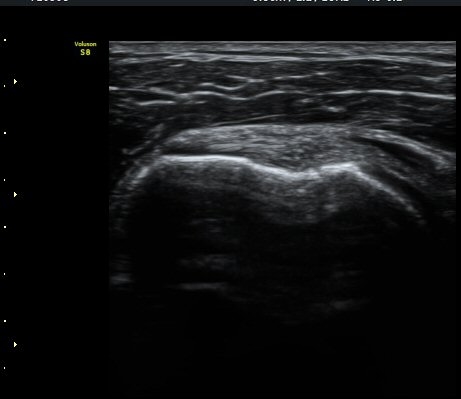

¾î±ú ¾Õ À̵ιڱ٠Ⱦ´Ü¸é°Ë»ç¿¡¼­ ÀÌºÎ¹Ú±Ù°Ç °í¶û ¾Æ·¡ ºÎÀ§¿¡¼­ À̵ιڱ٠ÀåµÎ ÁÖÀ§¿¡

¼ö¾×Àú·ù°¡ °üÂûµÈ´Ù(±×¸² 1, 2). °ß°©ÇÏ±Ù°Ç Á¾´Ü¸é°Ë»ç¿¡¼­ °ß°©ÇϱٰÇÀÇ °üÀý³»ºÎÀ§(±×¸² 3)